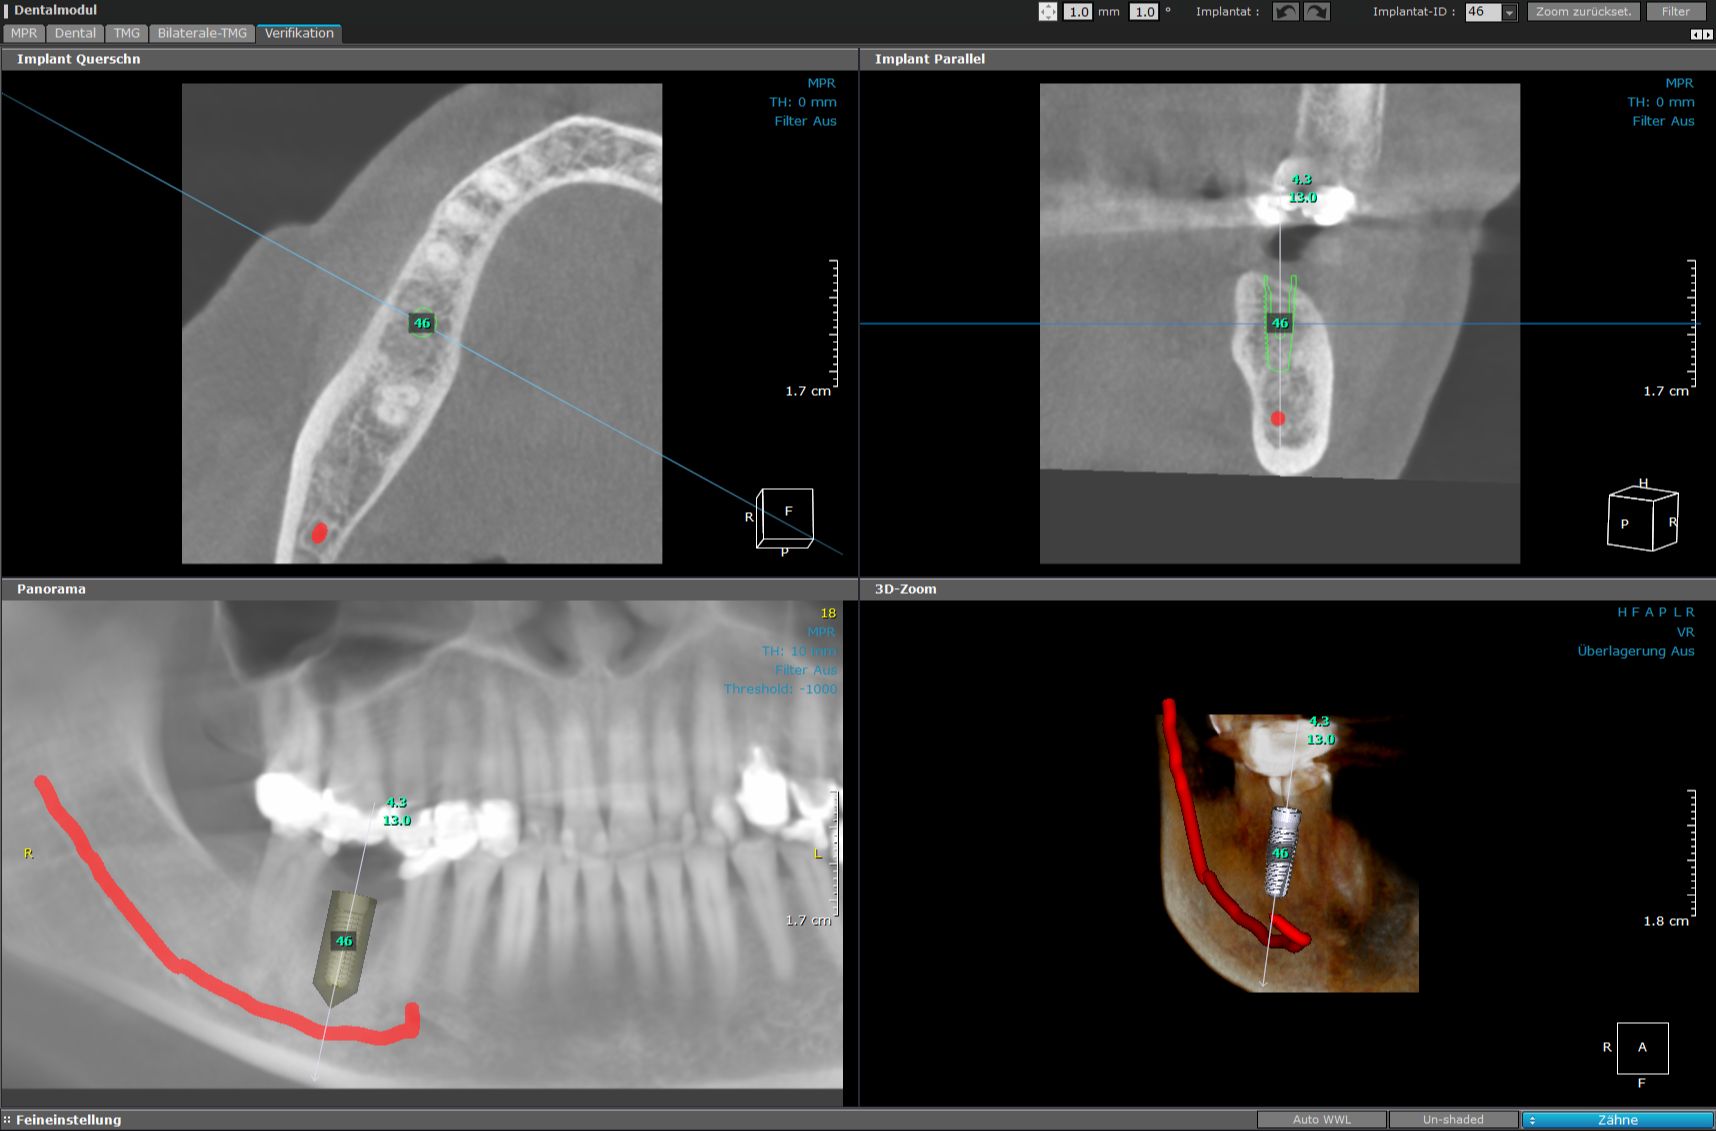

In der Implantologie ist die exakte Planung enorm wichtig. Am Computerbildschirm sehen wir, wo genau im Kiefer die Nervenbahnen verlaufen. Wieviel Knochenmaterial steht zur Verfügung und welches Implantat passt perfekt? Auf zehntel Millimeter genau können wir den Eingriff planen.

Virtuell werden alle relevanten Parameter definiert.